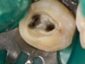

現在は、ドナーとなる歯の抜歯前に移植される側の処置を終了し、ドナーの歯を抜歯するとほぼ同時に、当院では3秒以内に受容側の中にドナーの歯を入れます。これはとても速いスピードであるといえ、このスピードで確実に行う為に、いろいろな研究を行い、CTスキャンのデータを応用した現在の移植のシステムを構築致しました。

このようにして移植された歯は、歯の根の表面にある歯根膜と言う組織がほぼ完全に保存され、生着(生きた状態で移植されて機能する事)する事によって、将来矯正治療で歯を移動する事もできますし、被せもの等を行えば全く移植歯である事は気が付かれないレベルで仕上がります。